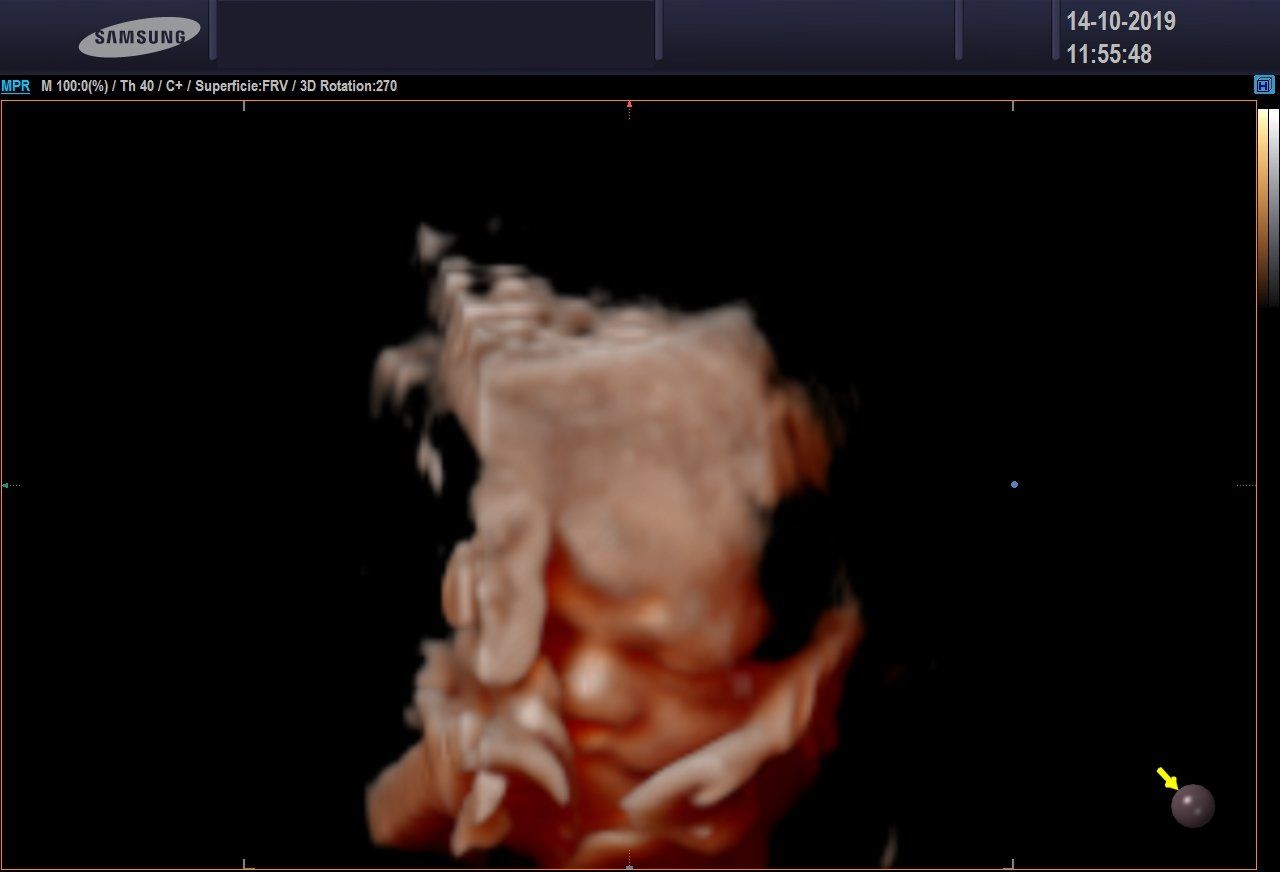

Ecografia 3D/4D

L'ecografia 3D consente di ottenere delle immagini statiche, non in movimento, ma in pratica delle foto delle fattezze del feto.